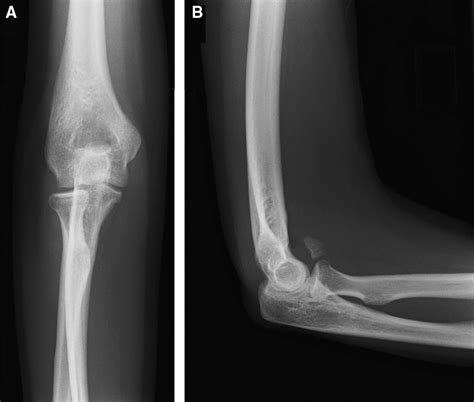

To truly grasp the significance of the ulnar coronoid process, one must first understand its structural position. The ulna is the bone on the medial side of the forearm (the side of the little finger). The proximal end of the ulna features a large notch known as the trochlear notch, which articulates with the trochlea of the humerus. The ulnar coronoid process forms the anterior (front) part of this notch.

This structure is triangular in shape and provides a stable surface for the elbow joint to pivot around. Because of its location, it acts as a physical barrier that prevents posterior (backward) displacement of the ulna relative to the humerus. If this structure is damaged, the entire joint becomes significantly more prone to dislocation or instability.

If you experience these symptoms following an impact to the arm, it is important to seek medical imaging, such as an X-ray or CT scan, to assess the integrity of the ulnar coronoid process.